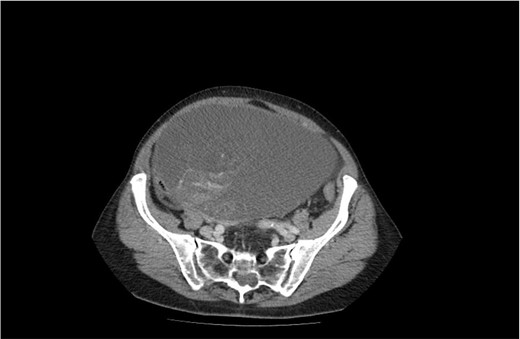

The second case is of a 62-year-old woman, admitted to a surgery clinic with abdominal distention, difficult defecation, and ultrasound data of a large tumor in the abdomen. CT describes a large tumor formation, reaching ventrally to the anterior abdominal wall, measuring 317/202/272 mm/d with a predominantly cystic structure (Fig. 3). The finding has a homogeneous content and multiple intralesional septa with a mass effect in relation to small intestine, main abdominal vessels, compress and dislocates the transvers colon and stomach. Operative treatment followed with laparotomy and evacuation of about 8 l of serous fluid from the cystic formation described on CT. Given the concerns about the presence of malignancy, a hysterectomy with adnexectomy and appendectomy was performed. Histopathologically, a multilocular mucinous cystadenoma of the left ovary was proven. The uterus has cystic endometrium and myometrium with intramural leiomyomas and adenomyosis, and the appendix with fibrinous-purulent periappendicitis. The patient recovered and was discharged on the seventh postoperative day without complications.